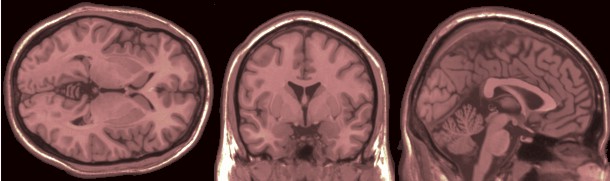

De beelden van de MRI-scan van de hersenen van Henk de Boer zijn binnen.

Grafisch ziet het er fantastisch en zeer inspirerend uit.

hersens henk

en dit zit erin.....